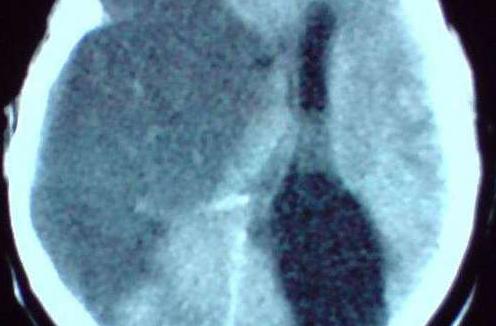

干细胞治疗脑梗塞后遗症 (脑梗塞后遗症最新治疗方法)